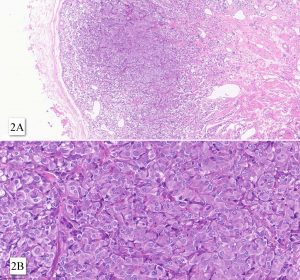

Paragangliomas of the bladder may have an epicenter in bladder muscularis propria, or in intact or ulcerated mucosa. At microscopy, the tumor shows a nested growth pattern with a Zellballen appearance. Nests are delineated by a delicate fibrovascular network and sustentacular cells. Tumor cells are round to oval may show pleomorphism or hyperchromasia. The cytoplasm may be eosinophilic or mirror the amphophilic to basophilic appearance of pheochromocytomas. Paragangliomas of the bladder usually involves muscularis propria and express GATA3 – two features that may lead to a misdiagnosis of advanced urothelial carcinoma.

Although rare, bladder paraganglioma should be considered in the differential diagnosis of bladder neoplasm with nested pattern of growth. An expanded panel of immunostain can easily distinguish urothelial carcinoma (keratin positive) from paragangliomas (keratin negative; positive for neuroendocrine markers).